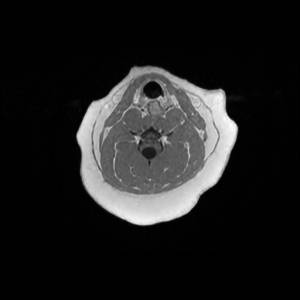

Main Gallery

Playing with a photo gallery function. It is possible to have multiple galleries, each within a namespace.